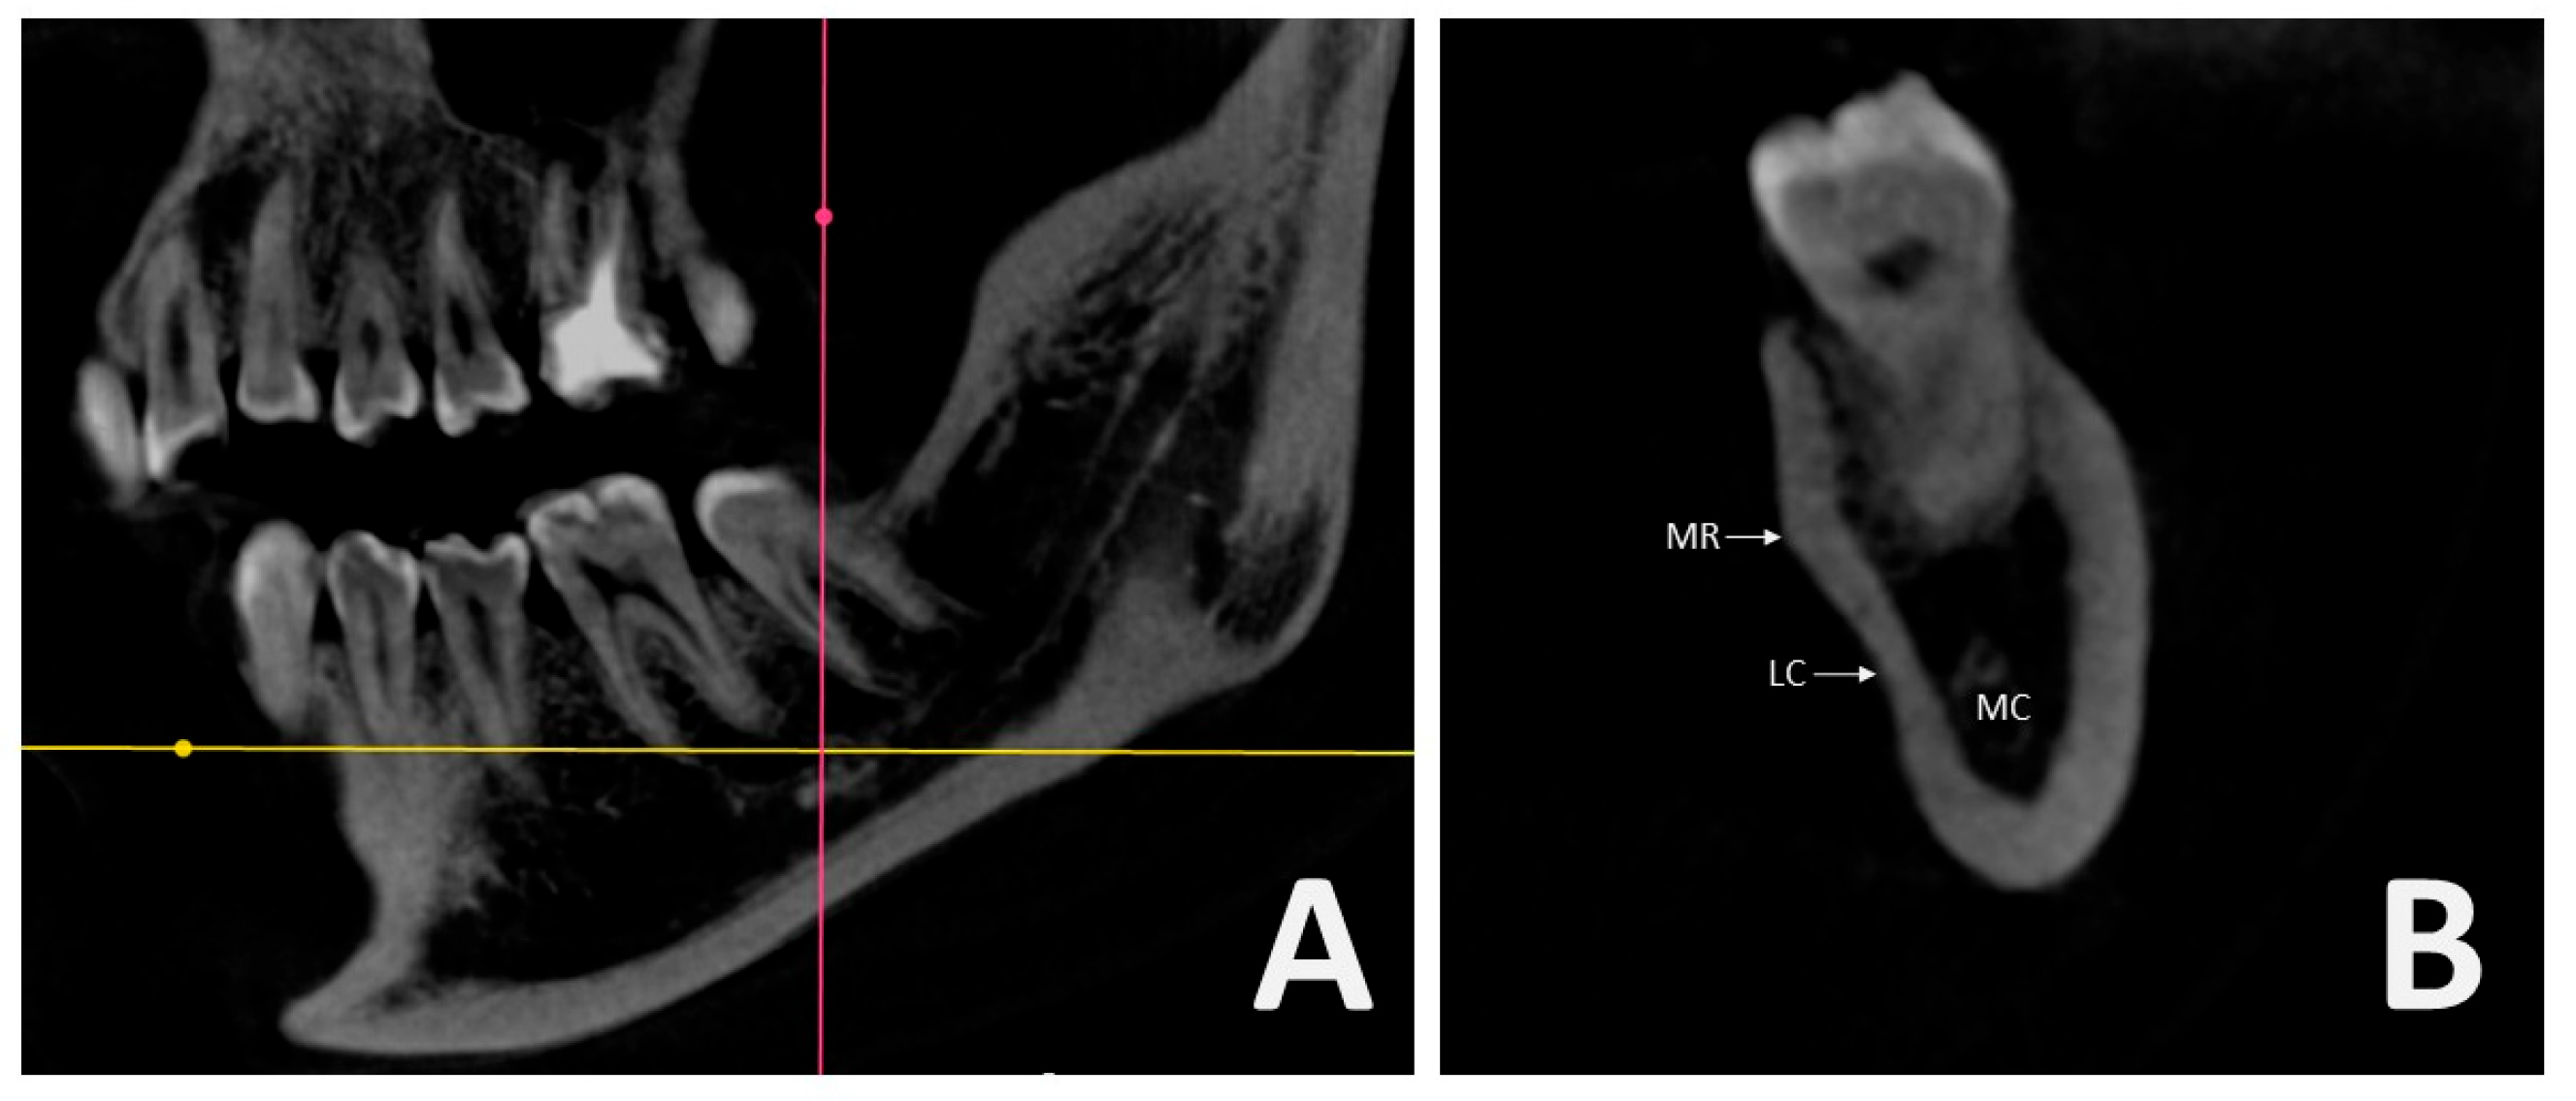

All scans were obtained using a single CBCT unit (Orthopantomograph OP300 Model, Instrumentarium Dental, Tuusula, Finland) with operating parameters of 5.0 mA and 90 kV, providing an 8 × 15 cm field of view and a voxel size of 0.25 mm. Digital Imaging and Communications in Medicine (DICOM) files were extracted from the CBCT datasets and analyzed using RadiAnt DICOM Viewer 2020.2 (64-bit trial version, Medixant, Poznan, Poland) software. Anatomical structures including the MR, LC, and MC were identified and assessed in the region between the roots of the first and second mandibular molars (Figure 1A,B).

Figure 1. Sagittal and cross-sectional hemimandible on CBCT: (A) Point between the second molar and first molar tooth root in the sagittal image; (B) Cross-sectional images showing mylohyoid ridge (MR), lingual concavity (LC), mandibular canal (MC).